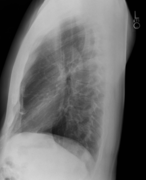

Lateral chest x-ray

Lateral views of the chest are obtained in a similar fashion as the posteroanterior views, except in the lateral view, the patient stands with both arms raised and the left side of the chest pressed against a flat surface.